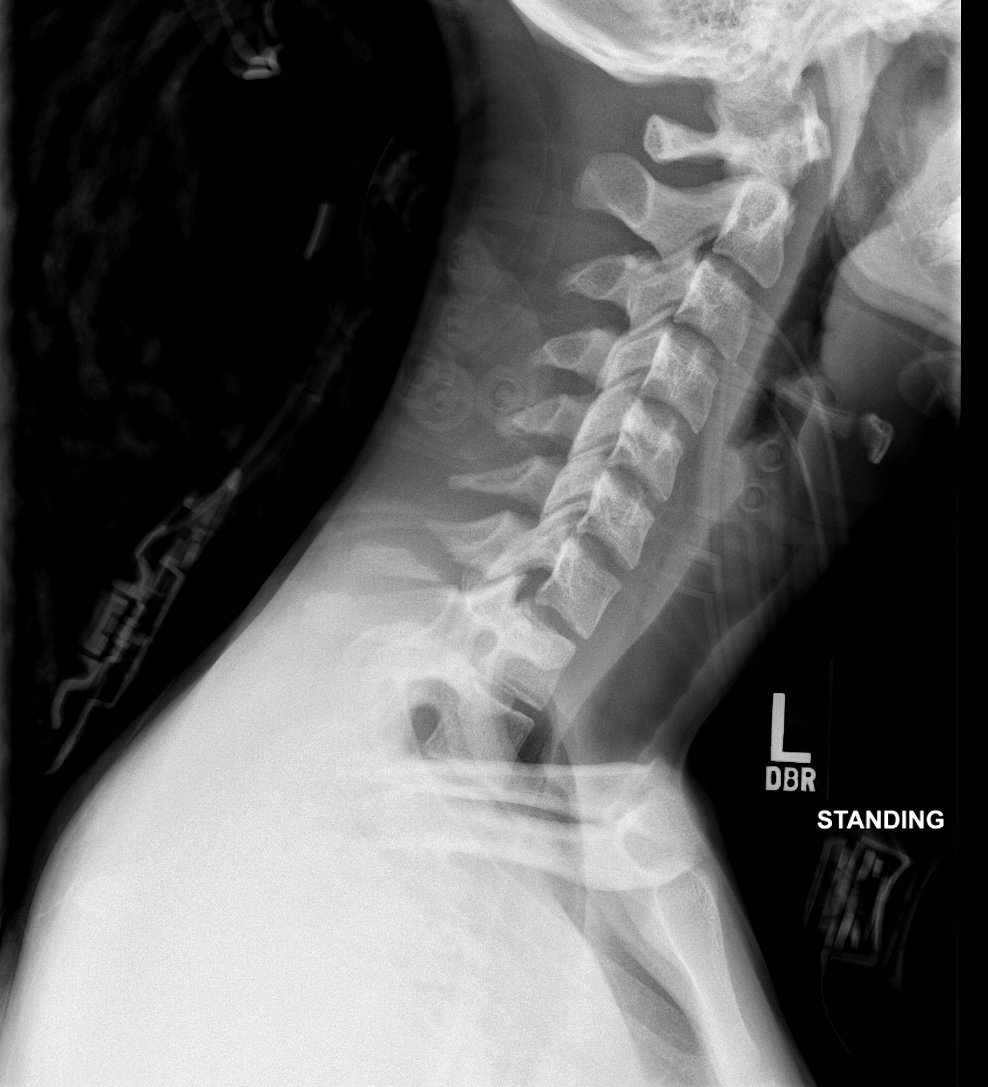

Info Images Findings Impression Reco/Acuity Case Images View Images / Launch Visage Case Notes History 2-month-old presents with decreased right arm movement, increased fussiness, and increased sleepiness for 2 days. Suspected non-accidental trauma. Exam Skeletal survey Prior Study none Dicom View Reference Material

Section 1 Submit Findings CB1550 Findings Skeletal Survey - Technique Check Skull AP/Lat Yes No Cervical and Thoracolumbar spine Yes No Chest X-Ray Yes No Ribs – Left/Right Oblique Yes No Abdominal X-Ray Yes No Pelvis with both hips Yes No Bilateral Humerus, Forearm, Hand Yes No Bilateral Femur, Tibia/fibula, feet Yes No Any additional lateral views of the extremities Yes No The exam is over or under penetrated. Yes No The exam may or may not be limited by overlying structures or soft tissues, body habitus, patient positioning, support devices, or motion. Yes No The area of concern is indicated by the patient, technologist, or care provider. Yes No The area of concern is included on the exam. Yes No Soft Tissues There is soft tissue swelling, indistinctness of fat/muscle planes, gas, or laceration in the area of clinical concern. Yes No There is an effusion, fat pad displacement, or fat fluid level. Yes No There is a radiodense or lucent foreign body. Yes No There are other densities, calcifications, post-surgical changes, or support devices in the soft tissues. Yes No Any support lines/tubes. Yes No Bone There is a break or interruption of the continuity of the cortical or cancellous bone. Yes No There is overriding of the trabeculae with apparent sclerosis. Yes No There is displacement of a fracture fragment. Yes No There is bowing of the bone in addition to the fracture at the apex of the bowed bone concerning for the greenstick. Yes No There is a spiral fracture of the leg concerning for toddler’s fracture. Yes No There is abnormal angulation or bulging of the cortical surface relative to the normal cortex which could be from a buckle or torus fracture. Yes No There is a displaced fragment which may be from avulsion by a tendon, ligament, or joint capsule or from a comminuted or other fracture. Yes No The stress trabeculae or other trabeculae of the cancellous bone are interrupted or otherwise abnormal. Yes No There is subperiosteal or endosteal reaction which could indicate a healing or subacute fracture or other abnormality. Yes No There is hard/soft callus formation. Yes No There is remodeling of the bone. Yes No There is a corner fracture or metaphyseal lesion that could be from nonaccidental trauma. Yes No There are multiple fractures of different ages. Yes No There are vertebral body/spinous process fractures. Yes No There are rib fractures. Location - posterior or lateral. Yes No There is scapular/sternal fracture. Yes No There are fractures of the digits. Yes No There are wormian bones. Yes No There are intrasutural bones. Yes No There is metaphyseal abnormality (lucencies, increased density, erosion) which may be from something other than injury such as stress, metabolic disease (e.g. rickets with loss or distortion of the zone of the provisional calcification), neoplasm (e.g. leukemia), heavy metals, inflammation, or infection. Yes No There are metaphyseal spurs. Yes No There are bony deformities involving multiple bones. Yes No The bones are gracile. Yes No There are non-healing fractures. Yes No There is/are focal or multifocal lytic/lucent, blastic/sclerotic or mixed density lesion(s) or other abnormality. Yes No Overall bone density is increased or decreased with or without thinning or thickening of the cortical or cancellous bone. Yes No Growth plates, ossification centers, apophyses The growth plate(s) is/are abnormal. Yes No There is widening of the physis from a fracture with or without displacement of the epiphysis (Salter-Harris I). Yes No There is a fracture through the physis which then extends into the metaphysis with or without angulation or displacement (S-H II). Yes No There is a fracture through the physis which then extends into the epiphysis and is intra-articular, with or without angulation or displacement (S-H III). Yes No There is a fracture through the metaphysis, physis, and epiphysis which extends into the joint space with or without angulation or displacement (S-H IV). Yes No There is narrowing of the physis from a compression fracture (S-H V). Yes No The apophysis, epicondyle, secondary ossification center, or accessory ossicle is displaced or otherwise abnormal. Yes No The ossification centers are underdeveloped. Yes No Joints and alignment There is an effusion, fat pad displacement, or fat fluid level. Yes No The epiphysis or subchondral bone is fractured, interrupted, flattened, compressed, impacted, displaced, or otherwise abnormal. Yes No There is an intra-articular loose body or chondrocalcinosis. Yes No The joint is widened, narrowed, dislocated, malaligned, or incongruent. Yes No There is pseudoarthrosis. Yes No Other findings There are developmental changes or other anatomic variants or other existing conditions that may or may not be contributing to symptoms which can or should be further evaluated non-emergently or are otherwise incidental. Yes No The remainder of the exam is abnormal for age. Yes No The lungs show focal airspace opacity. Yes No There is pneumothorax. Yes No There is organomegaly. Yes No There is intra-abdominal calcification. Yes No There is displacement of the bowel loops. Yes No There is free intraperitoneal air. Yes No The bowel loops are dilated/obstructed. Yes No There is paraspinal soft tissue abnormality. Yes No